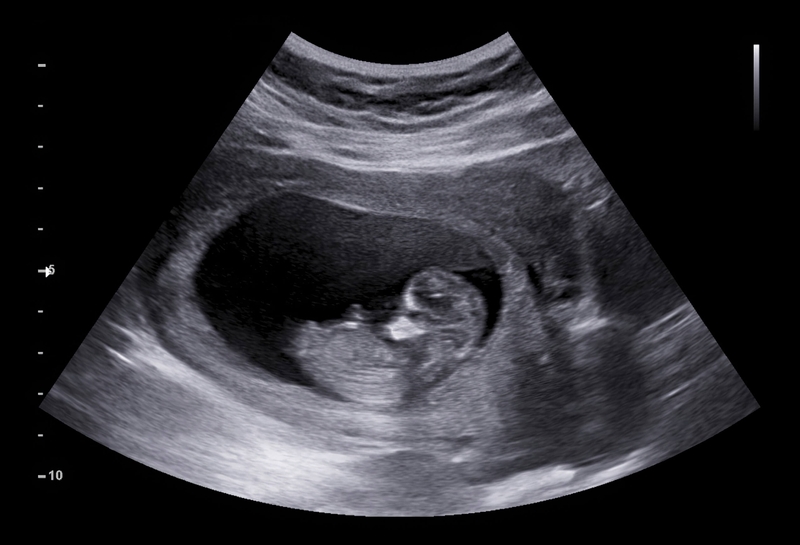

U cơ tim thai nhi bao gồm các khối u tâm nhĩ có thể rất nhỏ và nếu nằm ở vách ngăn hoặc khoang tâm thất sẽ giống như các nốt tăng âm trong tim (các vệt sáng nhỏ nhìn thấy trên siêu âm tim thai), do đó có thể được phát hiện bằng siêu âm, tuy nhiên, khá khó để phát hiện.

Để chẩn đoán u cơ tim thai nhi, các bác sĩ thực hiện siêu âm hai chiều và điện tâm đồ để theo dõi, đánh giá tiên lượng. Ngoài ra, siêu âm tim ba chiều hiện đóng một vai trò quan trọng trong việc phát hiện và mô tả đặc điểm khối u. Phương pháp này làm tăng độ chính xác và hiệu quả trong việc xác định kích thước khối u cũng như mức độ tổn thương các cơ quan lân cận.